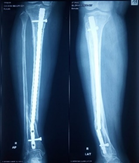

Case-I

19 years, male;

Broken ILIMN of femur (Ipsilateral fracture shaft of femur with tibia and fibula, H/O-poly-trauma) (Figure 1-4). Infection and non-union are the morbid complications of fracture management. Infections are more common in open fracture also caused by superficial surgical site infection. The incidence of infection in closed long bones fracture 1-2% and it is higher in open fracture, 5% Gustilo type-Ⅰ, 10% Gustilo type-Ⅱ and 15% Gustilo type-Ⅲ8 and surgical site infection (SSI) is 3.6 to 4.8%.9 The fracture complexity and soft tissue damage are the critical factors, influence the risk of infection.

Figure 1 X-ray broken IM nail after fall.

Figure 2&3 Post-operative x-ray after Ilizarov operation.

Figure 4 X-ray after union.